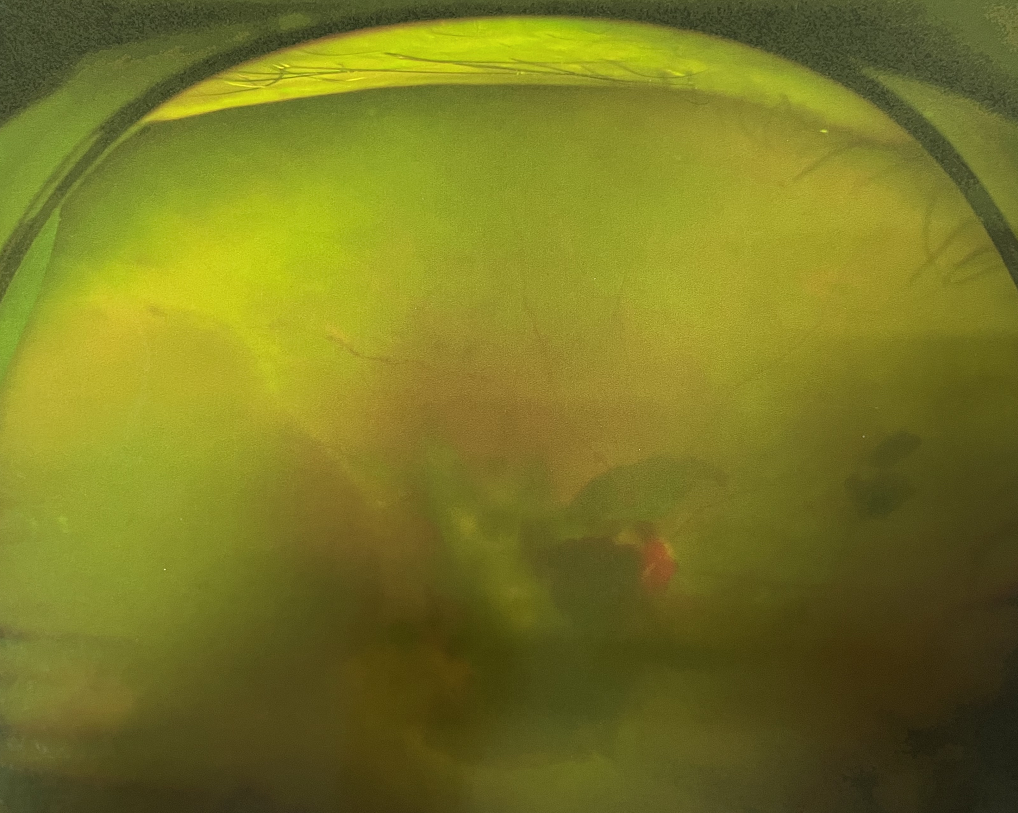

眼底出血是指眼內(nèi)視網(wǎng)膜出血,或玻璃體內(nèi)出血。眼底位于眼睛深處,所以這類出血只靠肉眼是看不到的,早期可能不紅、不痛、不癢,需通過(guò)專業(yè)的眼底檢查才可看到,往往短期內(nèi)就可造成視力驟降甚至失明!

同樣的,眼底出血也是一種癥狀,而非病種。誘發(fā)眼底出血的原因很多,常見(jiàn)的有全身性血管病和血液病、視網(wǎng)膜血管異常、機(jī)械性阻塞、炎癥性疾病或免疫復(fù)合物侵犯血管壁等。